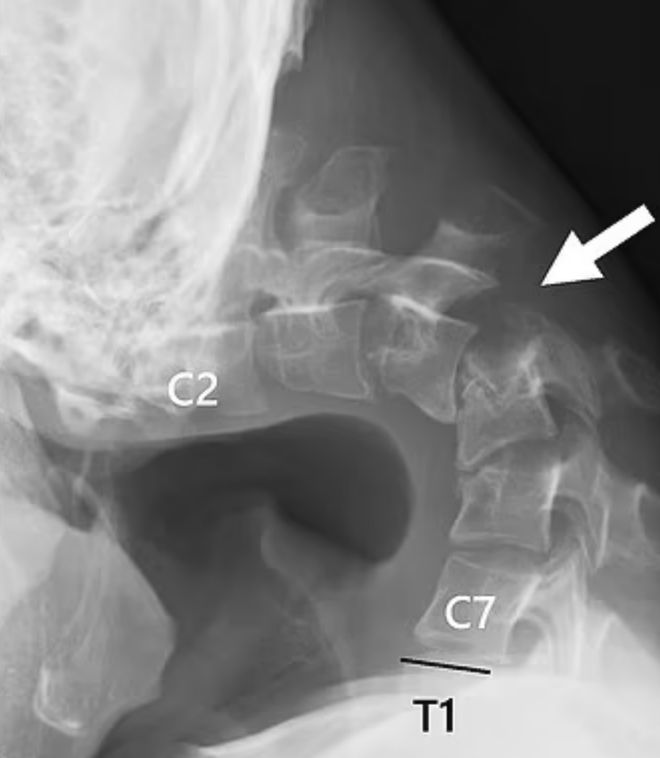

医院的扫描结果显示,他的颈椎已经变形脱臼,随着时间的推移,脊柱中形成了类似疤痕的组织。

医护人员最初尝试用颈圈来纠正该患者的“下垂头综合征”,但由于其反映佩戴设备时感到麻木,因此停止了这种治疗。医生后来选择了一系列外科手术,首先切除了患者的小段椎骨和颈部的一些疤痕状组织,然后将一系列螺钉和金属棒插入他的颈骨以矫正姿势。